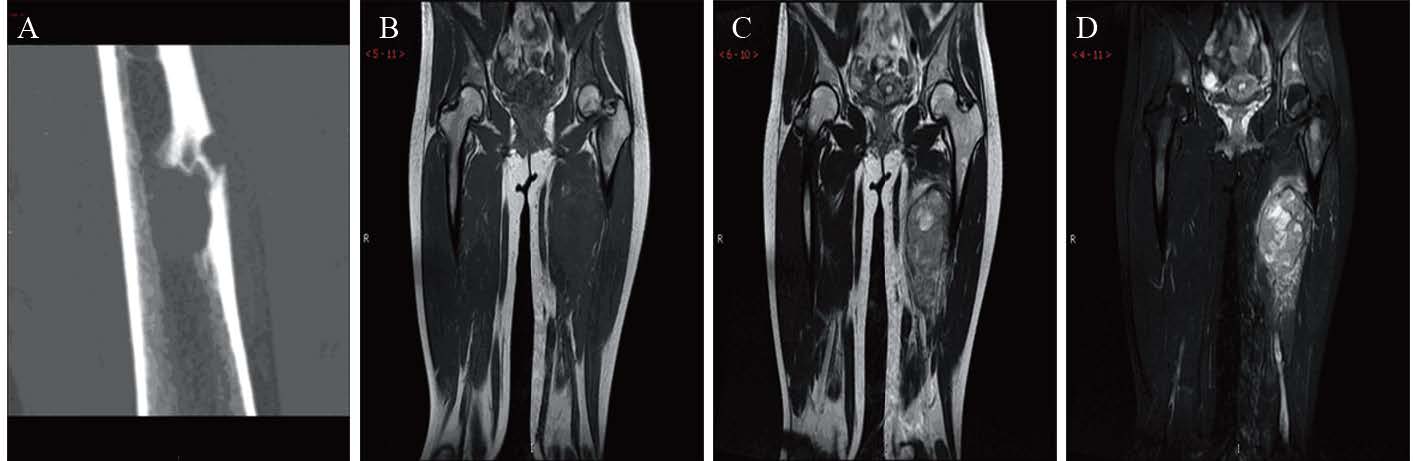

本组病例行CT、MRI、PET/CT或B型超声等影像学检查,均提示局部软组织肿块影、密度或信号不均匀,与邻近组织分界不清,部分伴有周围骨质破坏,增强CT或MRI呈不均匀强化,见图 3。初诊时50%(5/10)患者血清乳酸脱氢酶(LDH)升高至正常值的2~3倍;50%(5/10)患者外周血白细胞(WBC)数升高,以中性粒细胞升高为主,最高者白细胞为11.8×109/L,中性粒细胞高达91%。随着肿瘤手术切除或放疗、化疗后,LDH、WBC等指标均有所下降。

|

| A: CT 3D reconstrucion; B: T1WI; C: T2WI; D: T2WI-STIRA: CT scan showed a mass in the marrow cavity of right femur with bone destruction nearby; B-D: MRI showed the mass in the left leg had the similar T1 signal on the T1W1. T2W1 showed mainly long T2 signal. T2WI-STIR showed higher signal 图 3 外周型原始神经外胚叶瘤患者影像学检查结果 Figure 3 Imaging t results of pPNET patients |